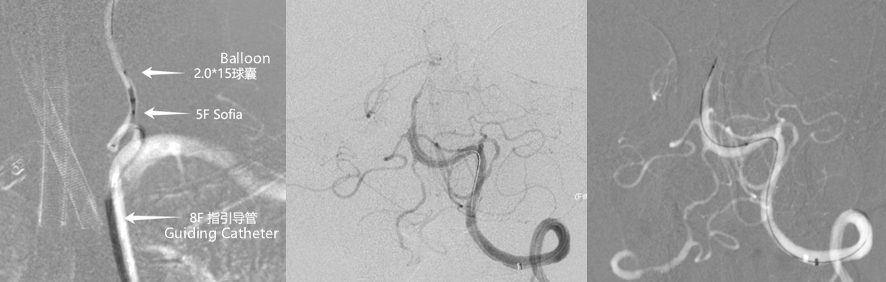

Left vertebral artery V1 segment was tortuous. A balloon-assisted DAC system was used to navigate through the tortuous segment. A 0.014-inch microwire failed to cross the occlusion due to torque control difficulty.

Switched to a 0.010-inch microwire, which successfully crossed the lesion and was advanced into the left superior cerebellar artery. Microcatheter angiography confirmed true lumen access. A Zenith Stent Retriever (4 mm × 20 mm) was deployed at the occlusion site.

After deployment of Zenith Stent Retriever, distal vessel branches reappeared. Post-thrombectomy angiography showed restored antegrade flow, but with residual severe stenosis.

3D DSA evaluation: Poor hemodynamic compensation at the lesion segment. Balloon dilation was considered risky due to inaccessibility and high risk of vessel rupture. Microcatheter was re-advanced across the stenosis. A 3.0 mm × 15 mm non-tapered intracranial stent was deployed slowly.